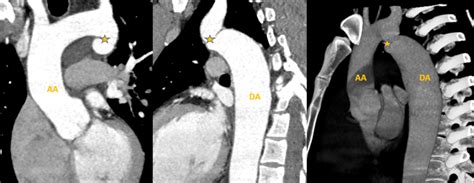

So, how do doctors actually figure out if your aorta is elongating or if there are other issues going on? It’s not like they can just, you know, see it without some help! The diagnostic process usually starts with a good old-fashioned physical examination and a review of your medical history and risk factors. Your doctor will listen to your heart and lungs and might feel for any abnormalities in your chest or abdomen. They’ll definitely ask about your family history, lifestyle, and any symptoms you might be experiencing. But to get a clear picture of the aorta itself, medical imaging is essential. One of the most common and accessible tools is an echocardiogram , or heart ultrasound. This uses sound waves to create images of your heart and the base of the aorta, allowing doctors to assess its size, shape, and function, and to check for any bulging or thickening. For a more detailed view of the entire aorta, doctors often turn to CT angiography (CTA) or MR angiography (MRA) . These advanced imaging techniques involve injecting a contrast dye into your bloodstream and then using CT or MRI scanners to produce highly detailed cross-sectional images of the aorta. They are excellent at showing the length, diameter, and any abnormalities like kinks, widening, or aneurysms. Sometimes, a standard chest X-ray might show signs of aortic enlargement, but it’s not as detailed as CTA or MRA. In certain situations, particularly if there’s concern about blood flow, a transesophageal echocardiogram (TEE) might be used, where an ultrasound probe is inserted down the esophagus to get closer images of the aorta. The choice of imaging technique often depends on what the doctor suspects, the patient’s specific condition, and the availability of the technology. The key takeaway here, guys, is that there are reliable ways to visualize and assess your aorta. If you have risk factors or concerning symptoms, don’t hesitate to ask your doctor about these diagnostic options.